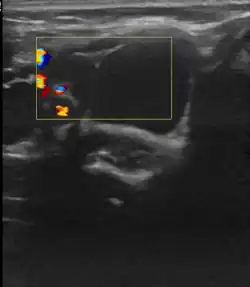

Пороки развития лимфатических сосудов в области головы и шеи чаще всего определяются при рождении или в первые годы жизни ребёнка, в возрасте до одного года в 60-80 % случаев[6]. Основными методами визуализации лимфатической мальформации являются ультразвуковое исследование (УЗИ) и магнитно-резонансная томография (МРТ). Данные исследования позволяют определить площадь и объём патологических тканей, размеры кист, топографию образования.

• Склеротерапия (склерозирование). Процедура включает в себя аспирацию содержимого кисты с последующей инъекцией склерозирующего агента, который вызывает рубцевание прилежащих стенок кисты. Склеротерапию проводят под ультразвуковой навигацией или с использование ЭОП’а. Склеротерапия не удаляет лимфатическую мальформацию, но она эффективно уменьшает объём поражения. Склеротерапия является методом выбора для лечения больших или проблемных крупно кистозных или смешанных лимфатических мальформациях[21].